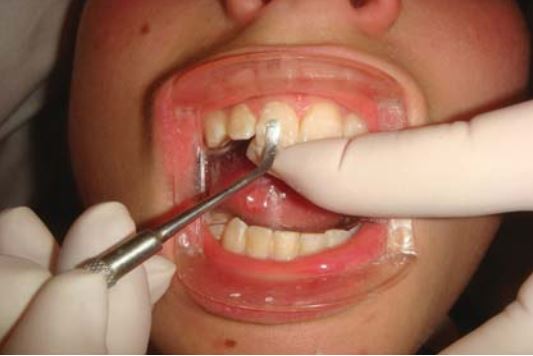

Bơm một lớp composite lỏng lên bề mặt răng hoặc bề mặt mảnh gãy để giúp tăng lưu giữ. Sau khi gắn lại mảnh gãy đúng vị trí thì sử dụng dụng cụ để loại bỏ composite thừa (H18.12).

Gắn lại mảnh gãy răng cửa hàm dưới thường khó vì kích thước rất nhỏ (H18.14).